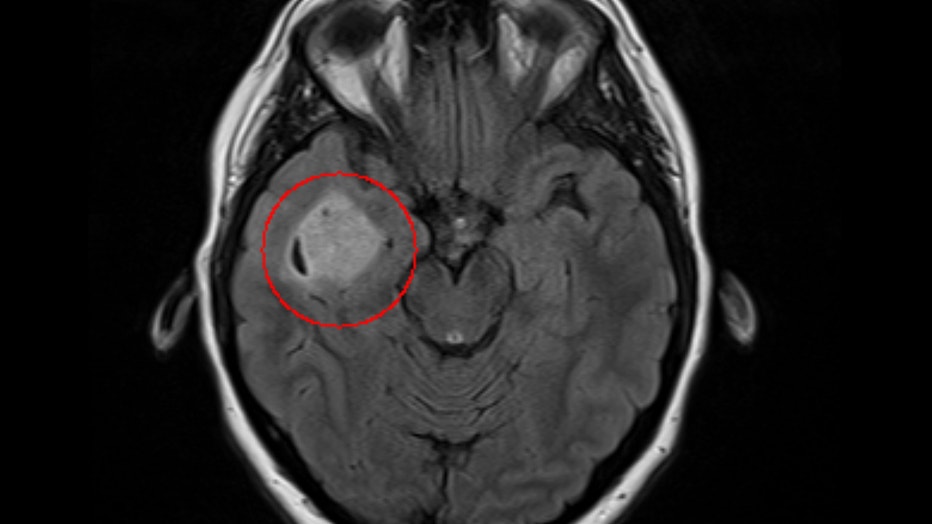

"When they give you a report, they start at the top of the body, and the first thing she said to me was, ‘You have a 2.3 by 2.4 centimeter mass in the right temporal lobe of your brain,’" Schaffer recalled. "That was not what I expected. I had no symptoms."

The scan detected a tumor the size of a walnut, a rare form of brain cancer. Surgeons at Phoenix's Barrow Neurological Institute were able to completely remove it just two months from her diagnosis. Andrea is grateful for the preventive MRI that ultimately saved her life.